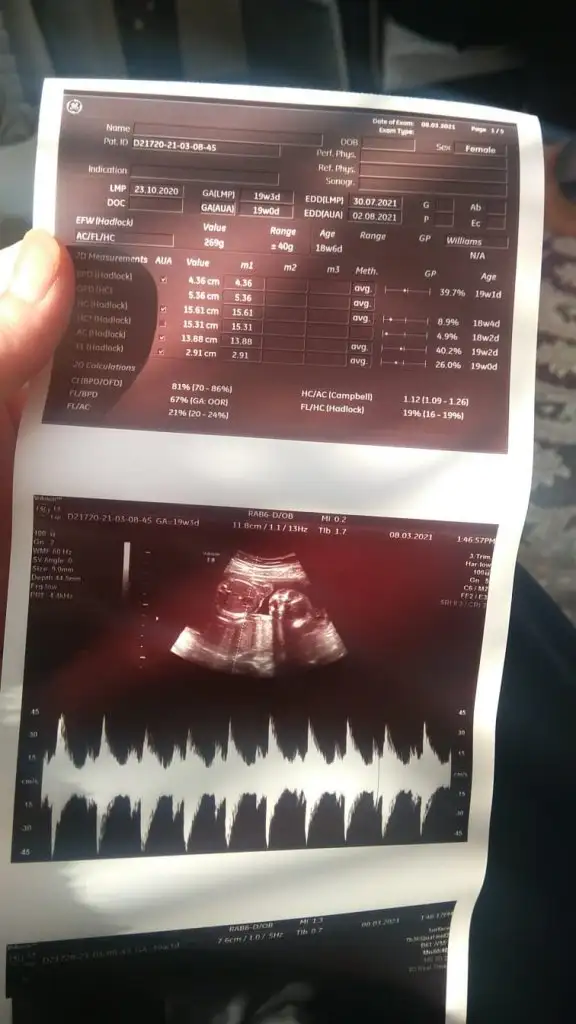

Merhabalar İkra Meyra hanım. 12. Haftada kız demiştiniz. O zaman bile Dr erkek demişti.Ama içimden inanmak gelmediği için bugüne kadar bekledim size yazmak için. Ve bugün 18+0 da kontrolümü takip eden Dr kız dedi. Farklı Dr.lara da göründüm onlar da kız dedi. Sonuç olarak tahmininiz doğru çıktı.Kız sanki